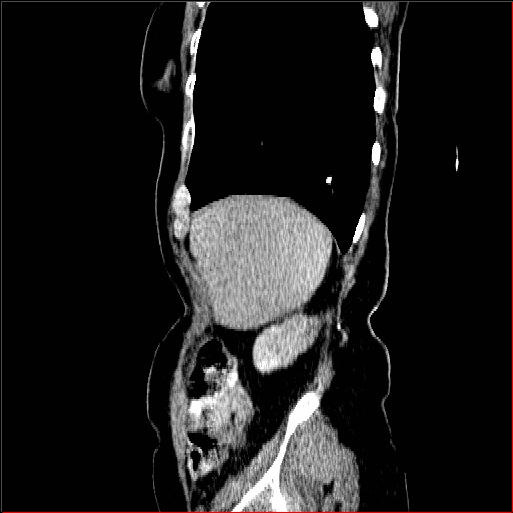

Liver Tumor

0.75×0.75×0.50.75\times 0.75\times 0.5

mm

512×512×768512\times 512\times 768

Figure 5: MAISI-v2 segmentation-guided results for five types of tumors. We show results for different voxel spacing and volume size to demonstrate the flexibility of MAISI-v2. Different Hounsfield Unit window is used to better show the contrast between tumor and normal tissues.